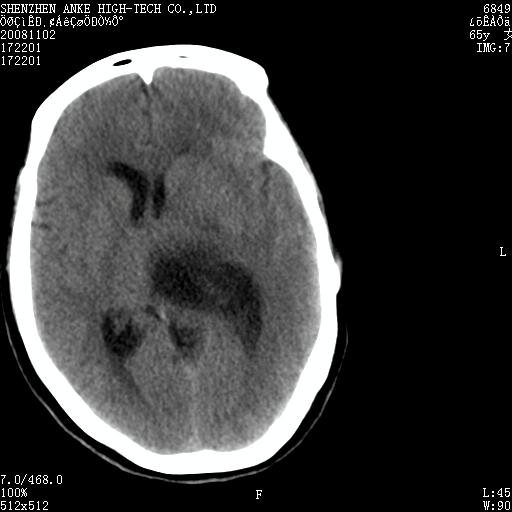

患者,女性,65岁,突发右侧肢体无力伴头痛,恶心、呕吐3小时.

1 左侧顶区圆形病灶,内可见钙化,考虑脑膜瘤,建议增强。2 左侧侧脑室病变,考虑神经上皮囊肿。

1)左侧顶区脑膜瘤可能性大;建议必要时行进一步检查。2)左侧脑室积水。

左顶部脑膜瘤,左侧侧脑室蛛网膜囊肿,建议增强.

左侧脑外占位(脑膜瘤)压迫脑实质、脑室侧室孔所致积水。支持!